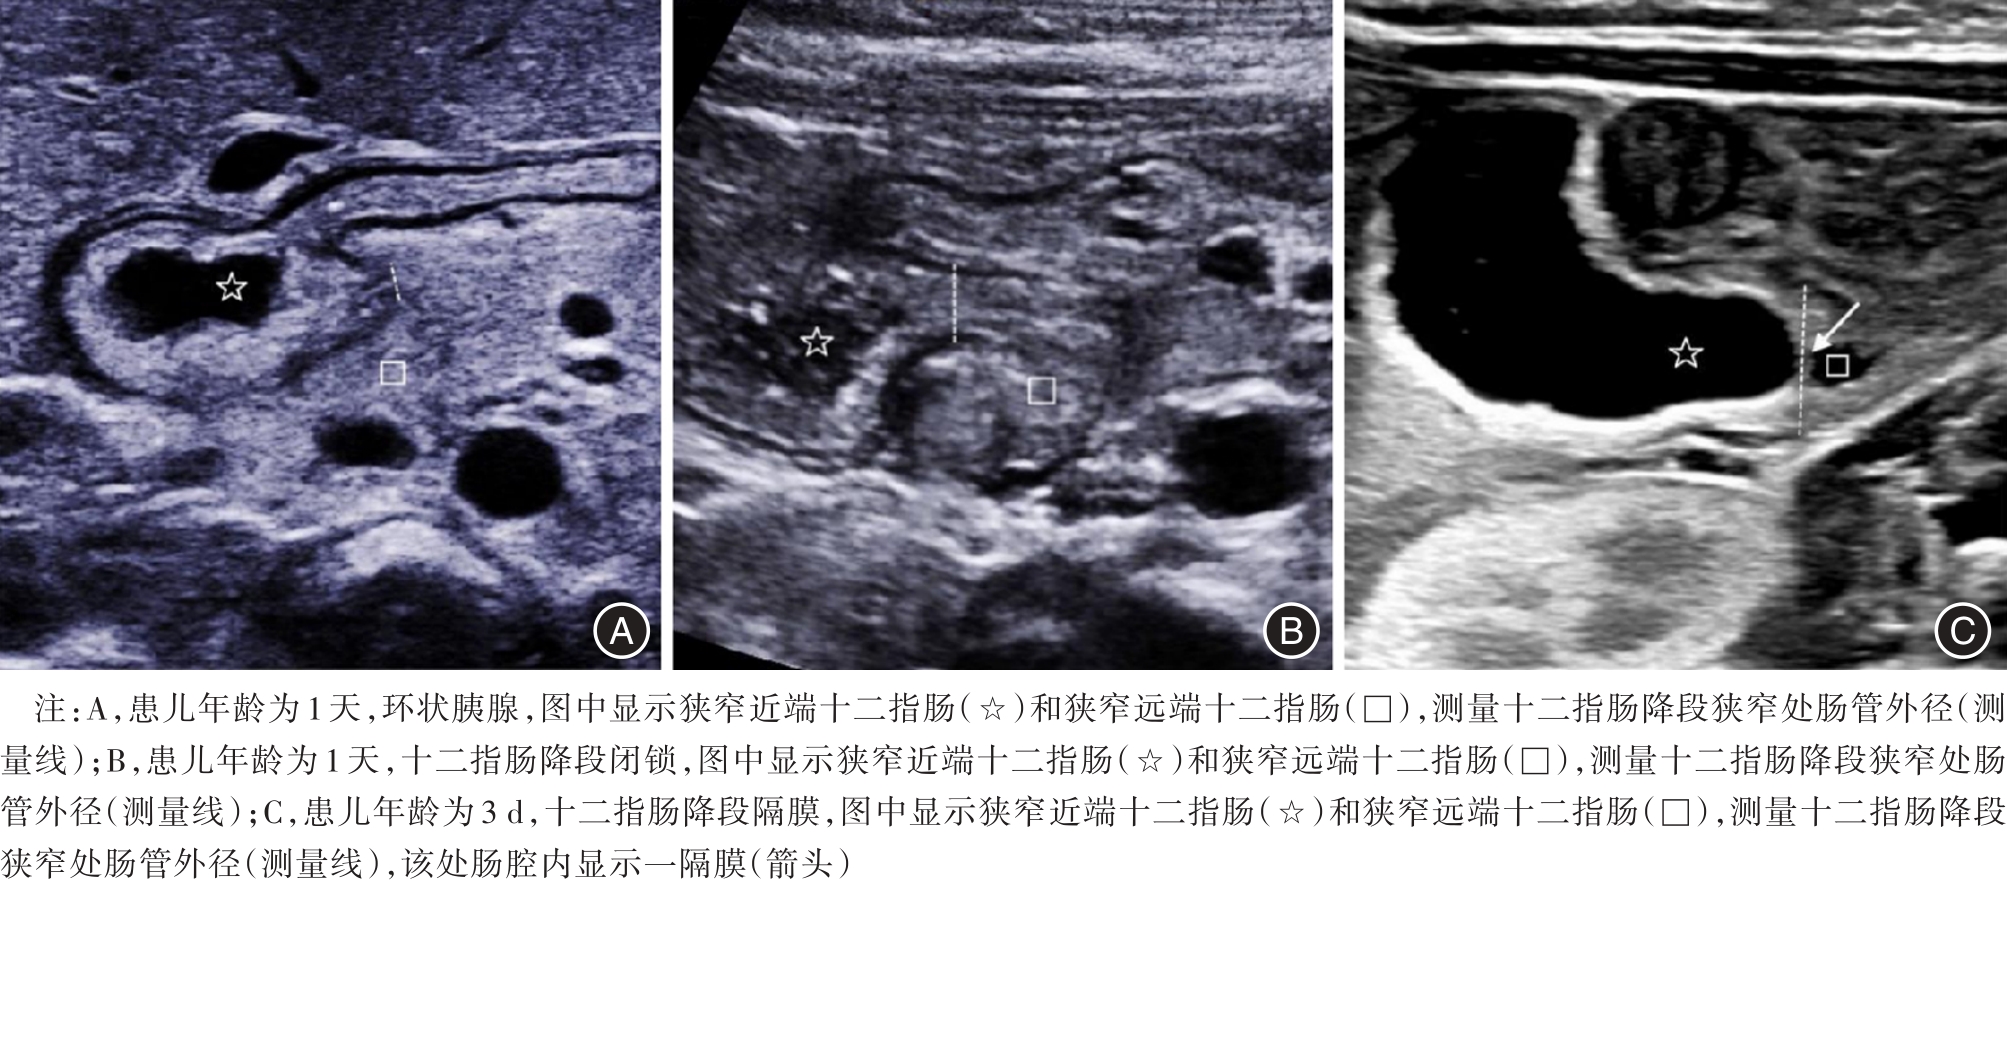

目的 探讨超声参数在新生儿环状胰腺诊断中的应用价值。 方法 收集2016年3月至2018年6月间,于本单位就诊的十二指肠降段梗阻的新生儿56例,均经上消化道超声造影检查。测量超声参数包括十二指肠降段扩张段外径(dilated duodenum diameter, DDD)、十二指肠降段扩张段肠壁厚度(dilated duodenum thickness, DDT)、十二指肠降段狭窄处外径(stenotic duodenum diameter, SDD)。据术中诊断情况分为环状胰腺组(A组)28例、十二指肠降段闭锁组(B组)3例、十二指肠降段隔膜组(C组)25例。采用单因素方差分析比较三组间的三种超声参数差异有无统计学意义,两两比较行LSD-t检验。如两两比较差异均有统计学意义,采用受试者工作特征曲线计算通过超声参数来诊断环状胰腺的曲线下面积及最佳截点值。 结果 三组中的DDD分别为(23.2 ± 2.4)、(25 ± 1.0)、(19.4 ± 2.6)mm,三组比较显示差异有统计学意义(F = 19.406,P < 0.001),两两比较显示A组、B组与C组相比,差异有统计学意义(t = 5.7,P < 0.05;t = 3.793,P < 0.05);A组与B组相比差异无统计学意义(t = 1.232,P > 0.05)。三组DDT分别为(3.0 ± 0.6)、(3.2 ± 0.4)、(2.4 ± 0.3)mm,三组比较显示差异有统计学意义(F = 12.487,P < 0.001),两两比较显示A组、B组与C组相比,差异有统计学意义(t = 4.695,P < 0.05;t = 2.778,P < 0.05),A组与B组相比,差异无统计学意义(t = 0.666,P > 0.05);三组中的SDD分别为(1.9 ± 0.3)、(3.6 ± 0.8)、(5.5 ± 0.7)mm,三组比较显示差异有统计学意义(F = 333.556,P < 0.001),两两比较,显示差异均有统计学意义(t = 5.521,P < 0.05;t = 6.142,P < 0.05;t = 25.828,P < 0.05)。采用SDD ≤ 2.3 mm来诊断环状胰腺的敏感性、特异性、阳性预测值、阴性预测值分别为96.4%、100%、100%、96.6%,曲线下面积为0.999。 结论 SDD可用于诊断新生儿环状胰腺。

Objective To investigate the clinical utility of ultrasound parameters in diagnosing neonatal annular pancreas. Methods A total of 56 neonates with descending duodenal obstruction underwent saline?contrast ultrasound examination. Ultrasonic parameters, including dilated duodenum diameter (DDD), dilated duodenum thickness (DDT), and stenosis duodenum diameter (SDD), were measured. The cases were categorized into three groups: annular pancreas (group A, n = 28), descending duodenal atresia (group B, n = 3), and descending duodenal septum (group C, n = 25). One?way ANOVA was employed to compare statistical differences among the three ultrasonic parameters across the groups, followed by LSD?t test for pairwise comparisons between two groups showing significant differences. Receiver operating characteristics analysis was conducted to calculate the area under the curve and determine the cut?off value if there were statistically significant differences observed. Results In group A, group B, group C, the diameters of DDD were measured as(23.2 ± 2.4)mm, (25 ± 1.0)mm, (19.4 ± 2.6)mm, respectively. When comparing these three groups, there was a statistically significant difference between group A or group B and group C in terms of DDD diameter measurements (t = 5.7, P < 0.05; t = 3.793, P < 0.05). However, no statistically significant difference was observed between group A and group B for DDD diameter measurements (t = 1.232, P > 0.05). The corresponding values for DDT were measured as (3.0 ± 0.6)mm, (3.2 ± 0.4) mm,and(2.4 ± 0.3) mm,respectively. When comparing these three groups,the results showed a statistically significant difference between either Group A or Group B compared to Group C in terms of DDT measurement (t = 4.695, P < 0.05; t = 2.778, P < 0.05). However,no statistically significant difference was found between Group A and Group B regarding the measurement of DDT (t = 0.666, P > 0.05). The SDD measurements in the three groups were (1.9 ± 0.3) mm, (3.6 ± 0.8)mm, (5.5 ± 0.7)mm, respectively. Statistical analysis using LSD?t test revealed significant differences between the three groups (t = 5.521, P < 0.05; t = 6.142, P < 0.05; t = 25.828, P < 0.05).The sensitivity, specificity, positive predictive value, and negative predictive value for detecting annular pancreas at a cutoff of 2.3 mm were determined to be 96.4%, 100%, 100%, and 96.6%, respectively, with an area under the receiver operating characteristic curve of 0.999. Conclusion SDD could be employed for the diagnosis of neonatal annular pancreas.